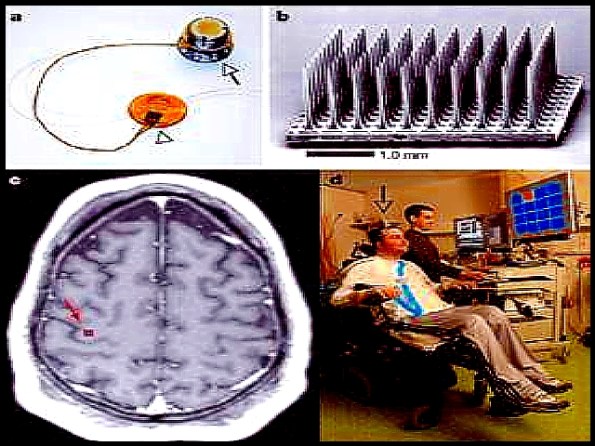

ROSSLYN, Va., March 6, 2000—Biomedical engineers have developed a prototype neuroprosthesis that a quadriplegic can use to grasp and manipulate objects just by thinking about it. The experimental device combines muscle-stimulating electrodes implanted under the skin with a computer sensitive to brain waves. Brain signals activate the electrodes that cause the hand muscles to contract. This research goes back 20 years for Hunter Peckham, Ph.D., professor of biomedical engineering at Case Western Reserve University and director of the Functional Electrical Stimulation Center, a consortium of the Cleveland VA Medical Center, Case Western and MetroHealth Medical Center. The work of Peckham and his colleagues has resulted in the first Food and Drug Administration-approved neuroprosthesis that uses electrodes implanted under the skin to give patients the ability to manipulate their paralyzed limbs. The device, called the Freehand System, was licensed by Case Western to a private start-up company, NeuroControl. The Freehand System is operated by a joystick-like device worn under the clothing. The patient moves the joystick with the opposite shoulder. The joystick activates implanted electrodes that stimulate muscles to open and close the hand. More than 150 patients are using the system.

Now Peckham’s laboratory is experimenting with other control devices. Clinical trials are under way on a system that uses an implanted sensor at the wrist to control muscle stimulation. It also enables patients to reach overhead. Another system in earlier stages of development is one that uses brain activity as detected by an electroencephalogram to control the neuroprosthesis. The new prototype, which has only been tested in the laboratory, couples an advanced, Freehand-like system with a monitor sensitive to brain waves. The monitor is worn like a shower cap dotted with electrodes. Wires lead from the electrodes to a computer that converts the brain signals into signals that open and close the hand. Jim Jatich, 51, of Akron, Ohio, a quadriplegic injured in a diving accident 20 years ago, has tested the system with some encouraging results. He gained mental control of the device after a series of training sessions in which he learned to regulate his beta-rhythm through biofeedback. During the training, Jatich learned to move a cursor up or down on a computer screen just by thinking about it. Then he was connected to the neuroprosthesis. By thinking about moving the cursor up, he opened his hand, and by thinking “down,” his hand closed. He can use the device to pick up objects like a drinking glass and a fork.

“Now if I think open, my hand just opens,” Jatich said. “It’s just weird. But I have to keep thinking open, open, open. If I think of anything else I lose control. So there’s a switch that locks my hand in the open or closed position.” “We just have to get rid of the cap, and that’s the next step. Then we’d have a totally implanted system under the scalp, and that would also produce a better signal,” Jatich said. Peckham’s group is also evaluating whether the brain signals will be sufficient to give Freehand users the full range of motion now available with the conventional device.